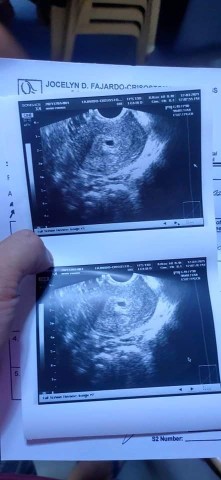

7 weeks sac pa ren :(

7 weeks from lmp wala pa daw embryo .. sac palang nakita sa transV. .pinababalik po ako after a week. tingin nyo po ba may pag asa pa? sobrang nakakapang lumo at nakakapang lata .. lungkot ng pasko #firstbaby sana.

todo iyak ko na nga po 7 weeks na daw po kasi sya sabi sa transV. pero eto po yung una kong transV ung 5 weeks daw po